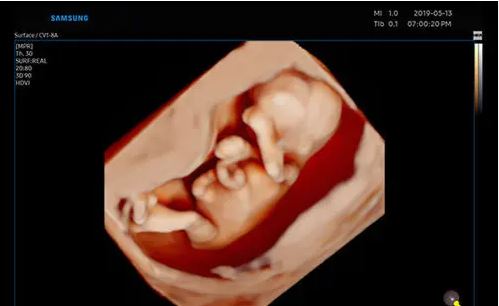

Modes d’imagerie: noir et blanc, doppler couleur, 3D/4D

Technologies d’imagerie redéfinies, optimisées par Crystal Architecture™: Crystal Architecture™ est une architecture d’imagerie qui combine CrystalBeam™ et CrystalLive™ tout en s’appuyant sur S-Vue Transducer™, pour fournir des images d’une clarté cristalline.

– CrystalLive™ est le moteur d’imagerie échographique Samsung le plus récent, avec un traitement d’image 2D, un rendu 3D et un traitement du signal couleur améliorés, dans lequel on obtient des performances d’image enrichies et un flux de travail efficace pendant les cas complexes.